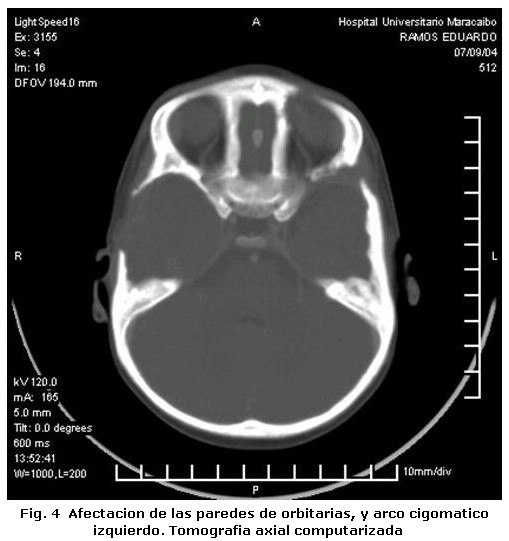

Un varón de tres años de edad con diagnostico de Histiocitosis de Células de Langerhans con afección ósea multifocal y otros sitios especiales fue referido al Servicio de Odontopediatría del Hospital Universitario de Maracaibo por el Servicio de Oncología Pediátrica del mismo Hospital, para valoración. El examen médico reveló, exoftalmos, palidez mucocutánea con pápulas eritematosas, lesiones hipercrómicas en miembros inferiores, dermatitis seborreica en cuero cabelludo, múltiples adenopatías cervicales y otitis supurativa recurrente. El informe de las pruebas de laboratorio indicó anemia y diabetes insípida. La biopsia de cuero cabelludo y el estudio inmunohistoquímico de la muestra tomada (Figura 1, 2 y 3) confirmaron el diagnóstico clínico, mientras que el examen de líquido cefalorraquídeo y médula ósea reportaron ausencia de infiltración. En las imágenes de resonancia magnética cráneo-facial, se evidenció realce anormal sugestivo de infiltración de huesos de base craneana y fosa anterior y media, mientras que la tomografía axial computarizada, reportó ausencia parcial de arco cigomático del lado derecho e imágenes osteolíticas en hueso temporal y pared orbitaria externa del mismo lado, acompañadas de lesiones similares en techo de orbita del lado izquierdo (Figura 4). Otros estudios, como tomografía de abdomen, pelvis y tórax, electroencefalograma, Rx de huesos largos, tórax óseo y columna, no revelaron hallazgos de interés. Durante la evaluación odontológica, la exploración extraoral evidenció exoftalmos y las lesiones de piel antes descritas; intraoralmente se registró la presencia de placa dental, gingivitis y hemorragia (Tabla 1), acompañada de movilidad dental, bolsas periodontales y recesión gingival (Figura 5) en la zona posterior izquierda de ambos maxilares (Tabla 2), además de caries dental y erupción prematura del 26. Radiograficamente se observaron lesiones osteolíticas, de bordes mal definidos, que medían aproximadamente entre 0,5 y 1,5 cm. de diámetro, localizadas en relación al 64, 65, 26, 74, 75, 85, también se observó agenesia de los gérmenes del 35 y 45 (Figura 6). Para el momento de la evaluación odontológica el paciente estaba recibiendo tratamiento con vasopresina y quimioterapia con vinblastina y prednisona. El manejo odontológico incluyo una fase inicial preventiva en la cual se instruyo a los representantes y al niño sobre hábitos de alimentación, higiene bucal y técnicas de cepillado y una fase quirúrgica llevada a cabo bajo anestesia general. Previa valoración sistémica y premedicación con antibioticoterapia se realizaron exodoncias del 65, 26, 74, 75 y curetaje de las lesiones. El resultado de la biopsia del tejido encontrado en los maxilares reportó un infiltrado inflamatorio severo, constituido por acumulo de linfocitos, histiocitos espumosos y células plasmáticas, mientras que el estudio inmunohistoquímico realizado con proteína S-100 y CD1a resultó negativo. Después de dos meses de seguimiento, el paciente cicatrizó favorablemente con persistencia en el 64 de recesión gingival, exposición de dos tercios de la raíz distal y movilidad leve. Radiograficamente se observan signos de osificación en las zonas intervenidas, sin embargo, es necesario seguir monitoreando al paciente para descartar la aparición de nuevas lesiones (Figura 7).

La Histiocitosis es una rara enfermedad cuyas manifestaciones clínicas son muy variadas; en el caso reportado, las características clínicas coinciden con algunas típicamente descritas en la literatura en relación a la edad, dermatitis seborreica, diabetes insípida, exoftalmos y lesiones óseas multifocales1-4. Este último tejido es uno de los más afectados1, nuestro paciente presentó lesiones en ambos maxilares y de forma bilateral en mandíbula, aunque en mayor grado del lado izquierdo. Desde el punto de vista clínico estas lesiones pueden semejar enfermedad periodontal y provocar movilidad dental2, la afectación ósea en nuestro paciente provocó erupción prematura del 26, recesión gingival y grado severo de movilidad dental; situación agravada por la presencia de irritantes locales. Un hallazgo que no hemos podido constatar con la literatura revisada, es la ausencia de los gérmenes del 35 y 45 sin relación con historia familiar, la cual podría catalogarse como agenesia, ya que de acuerdo a la secuencia y cronología dental, a los tres años edad deberían observarse signos de su formación7. Por otra parte, la ausencia bilateral de los gérmenes y la presencia de importantes lesiones osteolíticas solo en relación al 35, descarta la posibilidad de que las células infiltrantes hayan sido responsables de hallazgos similares en el lado contralateral donde la lesión era inferior a 0,5 cm. Sin embargo, es necesario descartar otros factores responsables de la agenesia dental antes de definir su etiología. El estudio inmunohistoquímico realizado a la lesiones intraorales no reveló positividad para S-100 y CD1a, a pesar de haberse encontrado positivos en la biopsia a inicial de cuero cabelludo. Estos marcadores además del CD207 han sido catalogados como específicos para la determinación de células de Langerhans; sin embargo se ha reportado hasta un 13% de resultados negativos para CD1a y un 7% para el CD2078. Los resultados obtenidos en la inmunohistoquímica de las lesiones maxilares, también podrían estar relacionados con los efectos producidos por la quimioterapia sobre las células infiltrantes. No obstante otros factores relacionados con la toma de la muestra no pueden descartarse como responsables de estos hallazgos. La decisión de seleccionar la cirugía, quimioterapia y/o radiación como tratamiento en la histiocitosis, dependen de la extensión de las lesiones, el grado de tejido involucrado y de la presentación unifocal o multifocal1,3. En este caso se decidió realizar exodoncias de los dientes con grado de movilidad severa y curetaje, con el fin no solo de tratar las lesiones maxilares sino de controlar el riesgo de infección. Se concluye que los maxilares al igual que los huesos del cráneo deben ser evaluados en pacientes con diagnóstico de Histiocitocis de Células de Langerhans, ya que estos pueden ser los únicos huesos afectados como sucedió en el caso estudiado. Por otra parte es importante resaltar que a pesar de la importancia de las pruebas inmunohistoquimicas en el diagnostico de esta enfermedad, su resultado siempre debe ser correlacionado con los hallazgos clínicos, radiográficos e histológicos encontrados en cada caso en particular.